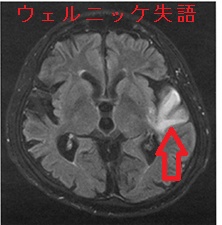

Wernicke失語(ウェルニッケ失語、感覚性失語:Wernicke's aphasia)は、側頭葉(上側頭回後部)にあるウェルニッケ野の障害によって起こります。ウェルニッケ野は、言語を思考に変換する感覚性言語野で、右利きの場合はほぼ全例、左利きの場合は約半数が左脳にあります。

- 言語理解の困難;話された言葉や書かれた文字の意味を理解できない

- 流暢な発話;流暢に話せるが、内容が支離滅裂、錯語(犬を猫と言う)が多い(言葉のサラダ)、相手の質問に合わない発言をしたり、意味不明な造語(新造語)

- 病識の欠如;間違った発話をしているのに自覚が乏しい

- 読み間違い(失読)